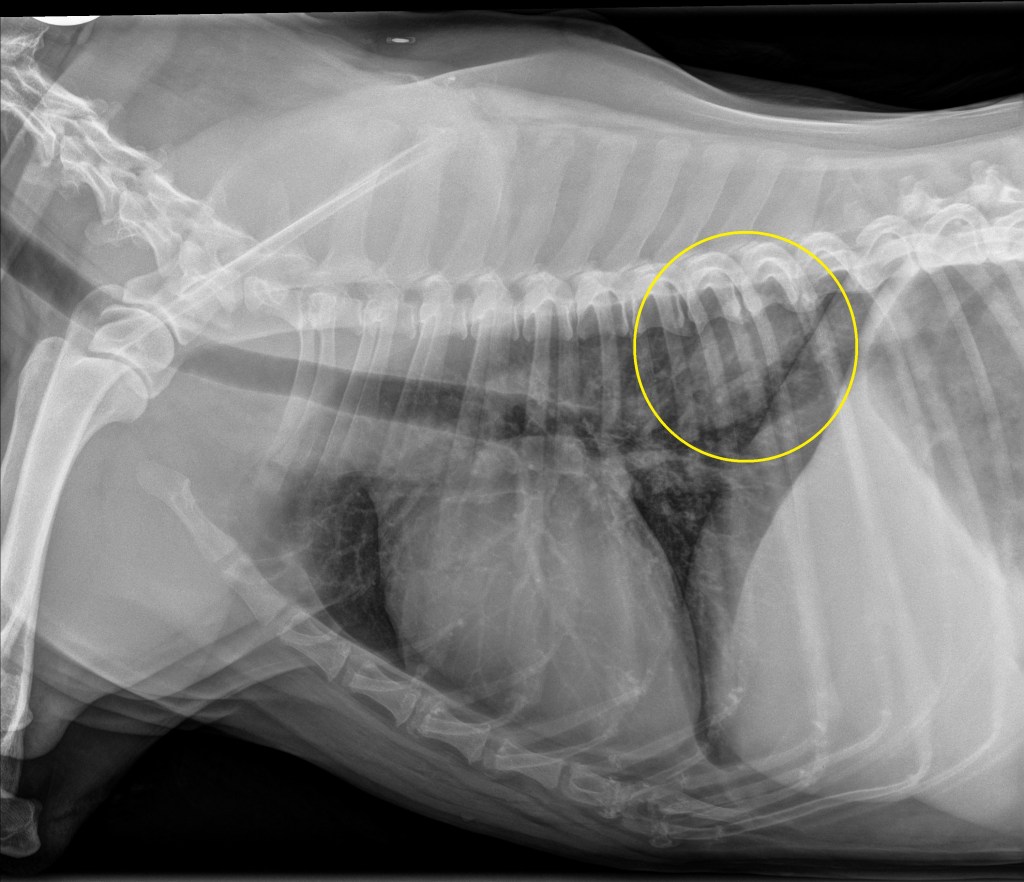

Thoracic radiographs: A mildly ill defined ovoid ~5.0 x 5.3 cm soft tissue opaque mass is located in the dorsal aspect of the right caudal lung lobe in the 7th-10th intercostal spaces. No evidence of intrathoracic lymphadenopathy. Concurrent mild bronchial and interstitial pattern throughout the lungs (likely an age appropriate finding). Findings consistent with primary (e.g. carcinoma) or slightly less likely metastatic or multicentric (e.g. lymphoma) pulmonary neoplasia. Much less likely differentials include granuloma secondary to fungal disease (patient lives in the northeast portion of the country with no travel history) or parasitic infection.